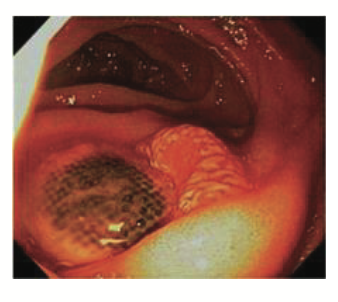

GAVE

classic antral watermelon appearance

often seen in women with autoimmune conditions

presents with IDA

Rx- APC and tranexamic acid